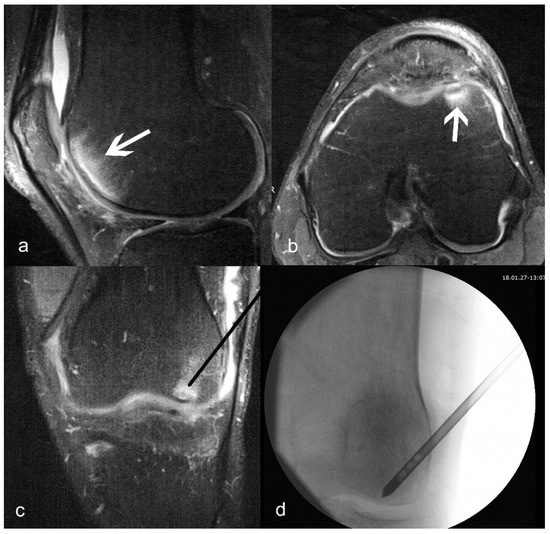

2.3. Surgical Treatment